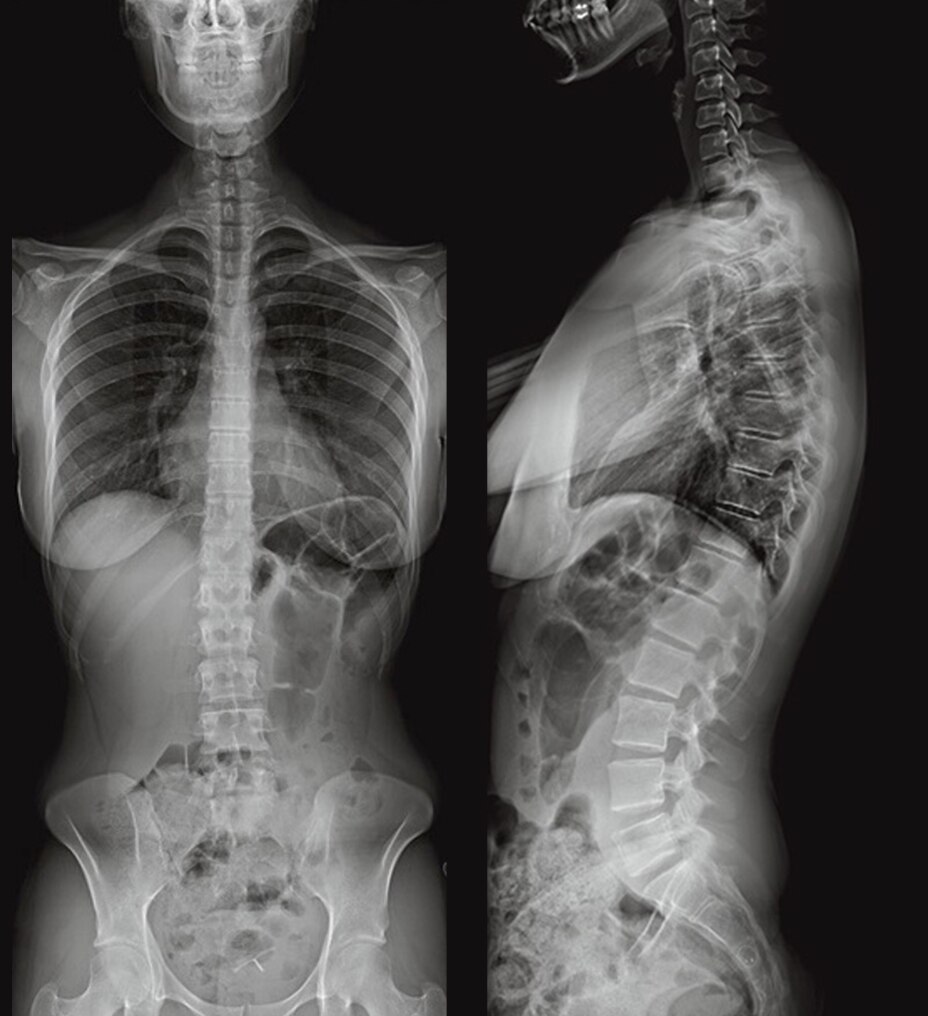

Designed for whole body imaging

LOGIQ Fortis expands your potential, with AI-based decision support and workflow solutions, specialty transducers, easy imaging and productivity enhancers. This all-in-one, high-performing ultrasound easily scales to fit your needs.